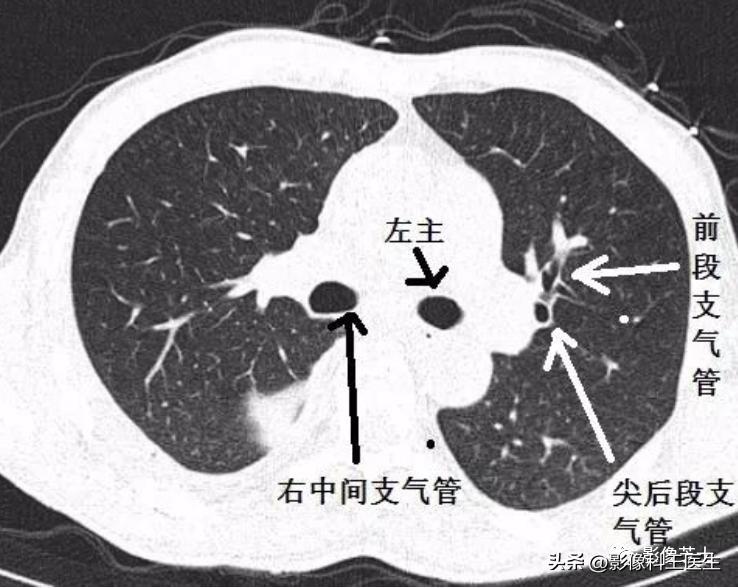

肺段、支气管分段CT解剖(详细标注)

肺部解剖分叶分段CT

中间支气管

中叶支气管

下叶支气管

肺的分段